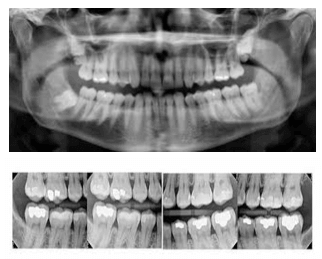

For example, compare 4-bitewing images and a panograph (pano). These are typical examples of images we generate to check for decay, bone levels, infection and tooth position.

The pano shown is about 16 microsieverts and the 4 bitewings are about 20 microsieverts

Pano = 16

4-Bitewings = 20